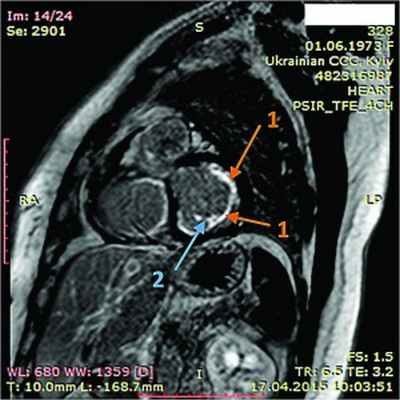

Рис. 1. Синусовая тахикардия. Желудочковые экстрасистолы (ЭС). Отклонение электрической оси сердца вправо. Отсутствие амплитудной динамики низковольтного зубца R в грудных отведениях

Рис. 2. Неравномерное значительное утолщение стенок ПЖ (парастернальный доступ, позиция по длинной оси)

Рис. 3. Тромб у верхушки ПЖ, уплотнение между листками перикарда в области верхушки (четырехкамерная позиция сердца)

Рис. 4. Сохраненная кинетика стенок ЛЖ, гидроперикард по ЗСЛЖ (парастернальный доступ, позиция по длинной оси, М-режим)

Рис. 5. Рестриктивный транстрикуспидальный кровоток (допплер)

Рис. 7. Динамическая томография, боковая проекция с контрастированием эндокарда (1) и тромба ПЖ (2)

Рис. 8. Динамическая томография, поперечная проекция с контрастированием полостей и тромба в ПЖ (1), гидроперикарда по всем стенкам (2)

Рис. 9. Динамическая томография, поперечная проекция с контрастированными полостями и стенками – неравномерное утолщение миокарда желудочков (1) с двумя апикальными тромбами (2)

Рис. 10. Динамическая томография, боковая проекция с контрастированием полостей и стенок – апикальный тромб ЛЖ

Рис. 11. Динамическая томография, косая проекция с контрастированием полостей и стенок – апикальные тромбы ЛЖ

В ходе серии динамических МРТ с контрастированием (рис. 7-11) выявлены массивные пристеночные тромботические наслоения в ПЖ, апикальный тромб ЛЖ.